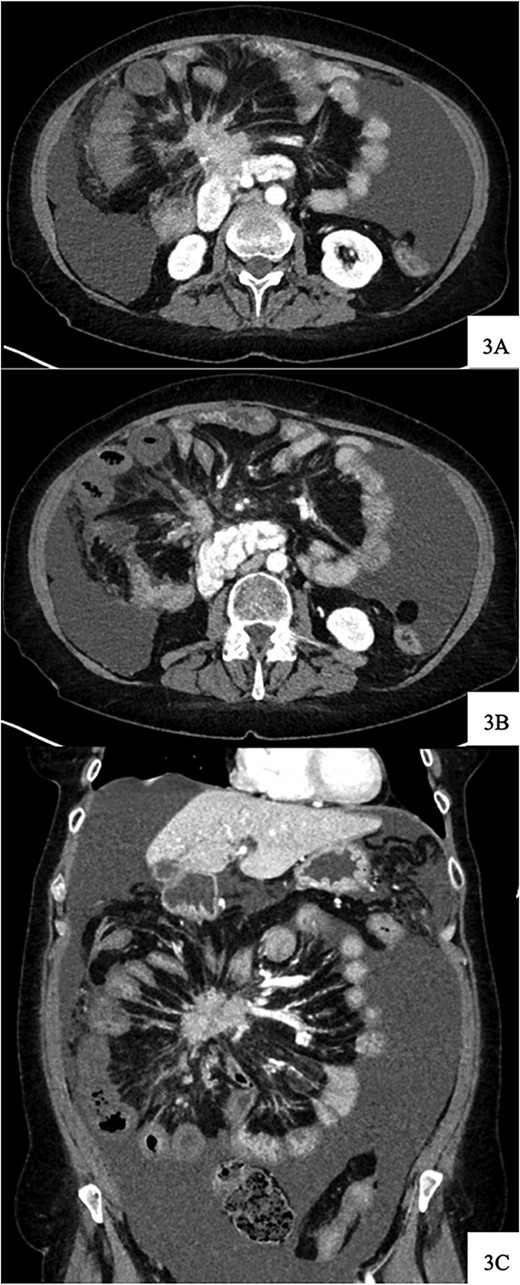

DOTATATE positron emission tomography-computed tomography scan revealing extent of metastatic disease.

Regarding her oncologic history, she was diagnosed with NET in October of 2017 when a computed tomography (CT) scan performed for intermittent abdominal cramping and diarrhea revealed a mass near the third portion of the duodenum and the root of the mesentery (Fig. 1). Biopsy of the mass revealed a well-differentiated NET. Further work-up with DOTATATE positron emission tomography (PET)/CT revealed a small bowel primary likely emanating from the terminal ileum as well as multiple lesions in the neck, chest, and liver (Figs 2 and 3). The periduodenal mass intimately involved the root of the mesentery, SMA, and SMV. She was initially treated with Lanreotide for many years with close monitoring and later underwent systemic treatment with Lutathera, a Peptide Receptor Radionuclide Therapy, from April 2020 to November 2020. She subsequently resumed Lanreotide in December of 2020, which she was on at the time of admission. Her disease remained largely stable on imaging over the next three years; however, her symptoms had been worsening over the few months leading up to her presentation.

DOTATATE positron emission tomography-computed tomography scan at time of diagnosis in November 2017 revealed a small bowel primary tumor in the right lower quadrant consistent with terminal ileum (A) as well as the periduodenal mass near the root of the mesentery (B). Coronal reformatting redemonstrates the primary tumor (C) and mesenteric mass (D).